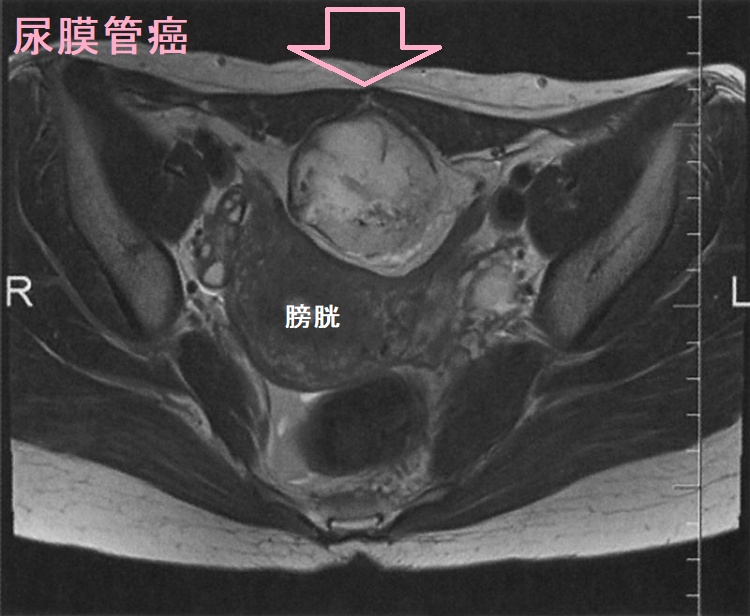

尿膜管癌 腹部MRI T2強調水平断像

尿膜管癌 腹部MRI T2強調水平断像;膀胱頂部から臍(へそ)に掛けて、膀胱を圧迫する腫瘤を認めます。